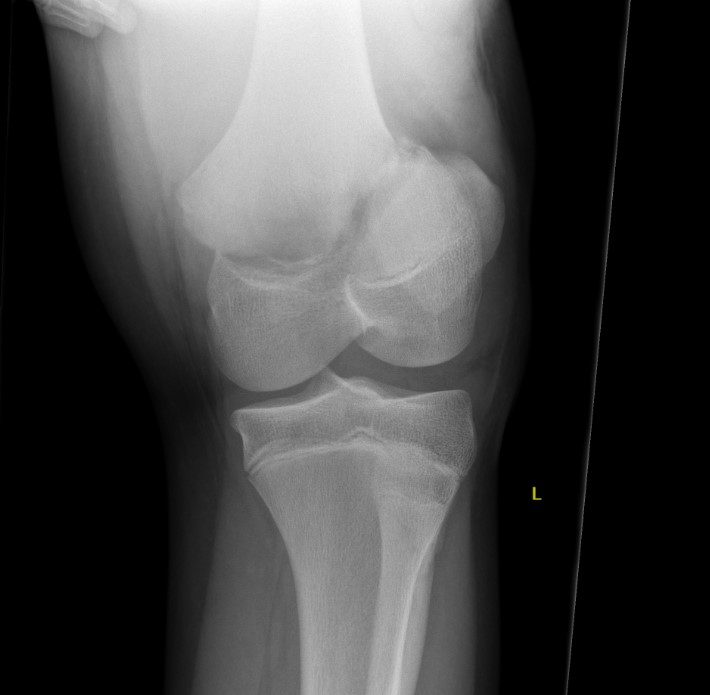

Xray

Salter Harris I

Salter Harris II